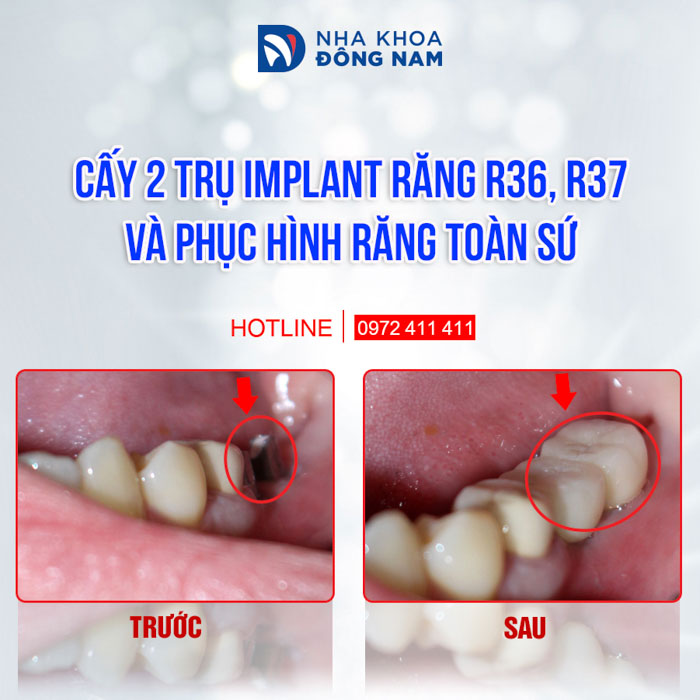

- Chứng nhận “Dịch Vụ Hoàn Hảo” dành cho dịch vụ Cấy Ghép Implant và Phục Hình Răng Sứ do chính khách hàng bình chọn.